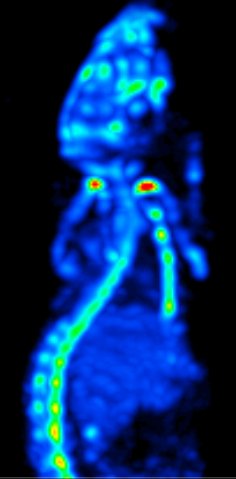

Der hochentwickelte Pinhole-Kollimator mit mehr als 75 Löchern und mit 3D Focus-Technologie ausgestattet, erreicht zusammen mit der hochmodernen Elektronik eine ultrahohe Auflösung von: <0,35 mm bei Maus-Bildgebung und <0,9 mm bei Ratten-Bildgebung. Mit der Niedrig- und Hochdosis Ganzkörper Bildgebung erreichen Sie höchst mögliche Auflösungswerte. Alle Daten werden automatisch im List-Mode aquiriert.